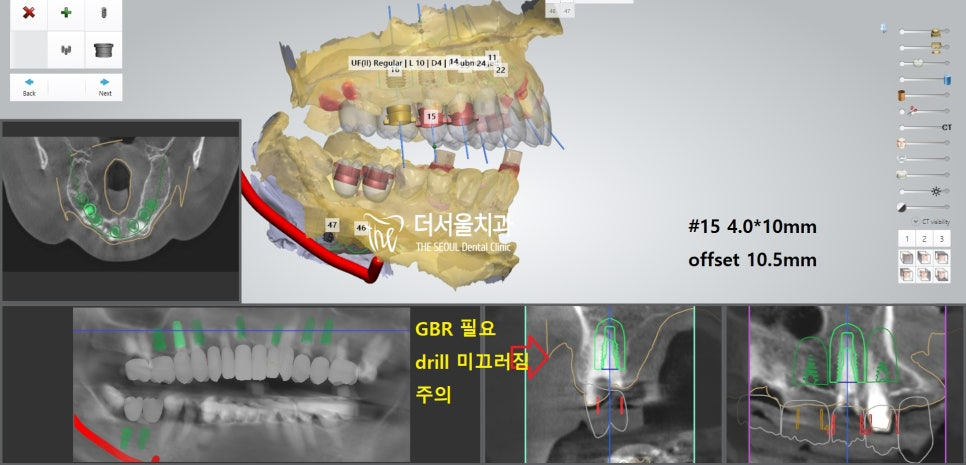

더서울에서 항상 했던 그대로

디지털 분석을 통해 인접치,

주변 조직과의 위치 관계를 파악했습니다.

계산된 위치에 맞춰 픽스쳐를 심어드렸습니다.

개수가 많기 때문에 걱정이 되었지만,

미리 제작된 가이드를 사용하여 수술을 진행하였더니

즉시식립 임플란트 과정을

정확하고 안전하게 끝마칠 수 있었습니다.